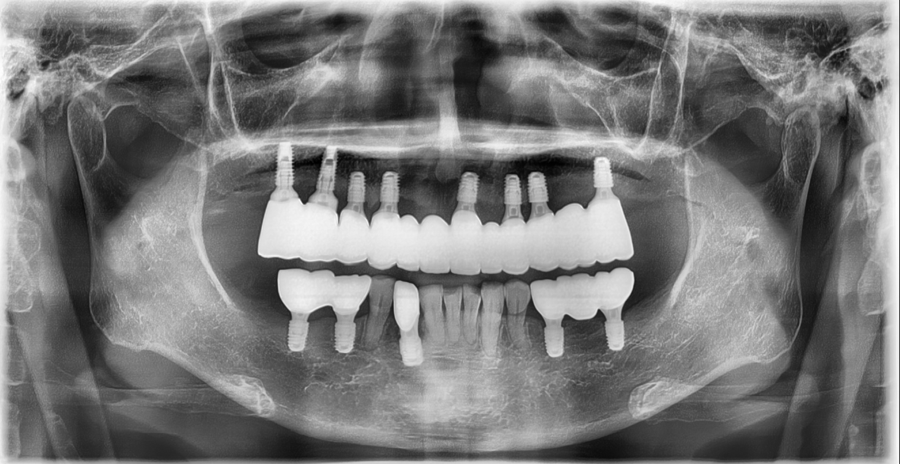

Detailed analysis based on CT diagnosis

At Seoulove Dental Hospital,

we use 3D CT and an oral scanner

to analyze the bone thickness, degree of resorption, nerve position, gum height,

and occlusion.

The test results showed that in several areas of both the upper and lower jaws,

the bone had been significantly resorbed,

and

bone grafting (GBR) was absolutely necessary in multiple areas in order to place implants.

Based on this diagnosis,

a specialist in oral and maxillofacial surgery trained at Seoul National University and a prosthodontics specialist

developed the overall treatment plan together.

Extraction + implant placement, performed at the same time

After extracting the old prostheses and weakened teeth,

we placed implants immediately in the necessary areas.

Areas lacking sufficient bone were supplemented with GBR to ensure stable support.

The angles of the upper and lower jaw implants were precisely placed in the preplanned positions based on CT data.